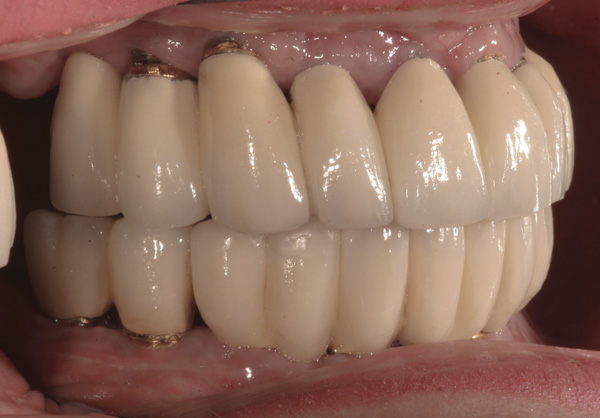

Case 5 – Conical Abutments Used As Temporary Abutments

Background: The patient in this case presented with a failing dentition due to generalized severe periodontal disease with secondary endodontic lesions. She adamantly refused to wear removable transitional prostheses. Full maxillary and mandibular extractions were performed in the first phase of treatment. Not all implants could be placed in this initial phase due to the need for healing of certain grafted sites. The implants placed in this first phase were loaded with conical abutments and, in some cases, their angulated counterparts (Figure 16 and Figure 17). These stock titanium abutments were selected to avoid the need, as in Case 3, to change or remill the more costly custom abutments. They also have the advantage of making it unnecessary to use temporary cement near and around surgical sites, as they use occlusal screws only for retention.

Results: Stock titanium abutments were used until all tissue healing was achieved and the secondary implants had healed. Figure 18 shows the maxillary and mandibular custom abutments inserted. Figure 19 shows a close-up of the patient’s right side quadrants, depicting the final case 15 months after initial treatment began. Recession can be seen around units corresponding to teeth Nos. 5 and 6. In this case, the authors attempted to minimize recession susceptibility by employing stock temporary screw-retained abutments during healing phases throughout the initial stages of the treatment plan. Despite these efforts, recession still occurred in certain areas where the implants were labially placed. Since the photographs shown in this case were taken, an unsuccessful attempt was made by the patient’s surgeon to graft soft tissue around these sites with recession.

Figure 16 First-phase implants loaded with conical abutments and, in some cases, their angulated counterparts.

Figure 16

Figure 17 First-phase implants loaded with conical abutments and, in some cases, their angulated counterparts.

Figure 17

Figure 18 Custom abutments inserted.

Figure 18

Figure 19 Final result 15 months after initial treatment began, showing patient’s right side quadrants.

Figure 19